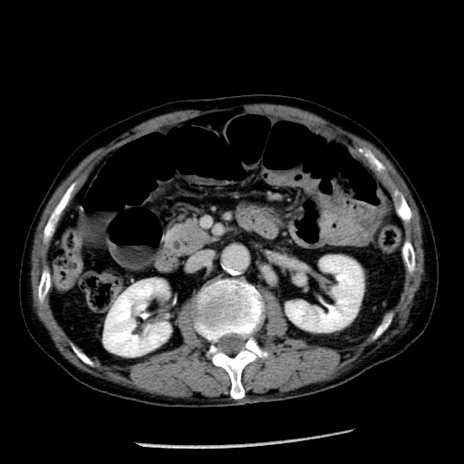

症例26(横断像)

【症例】80歳代男性

【主訴】嘔吐

【現病歴】昨晩2回嘔吐あり、今朝になっても嘔吐あり。来院。

【既往歴】胃潰瘍

【身体所見】意識清明、BT 37.6℃、BP 166/95mmHg、HR 100bpm、SpO2 97%、腹部:平坦・軟、腸蠕動音聴取良好、圧痛なし。

【データ】WBC 21900、CRP 1.46